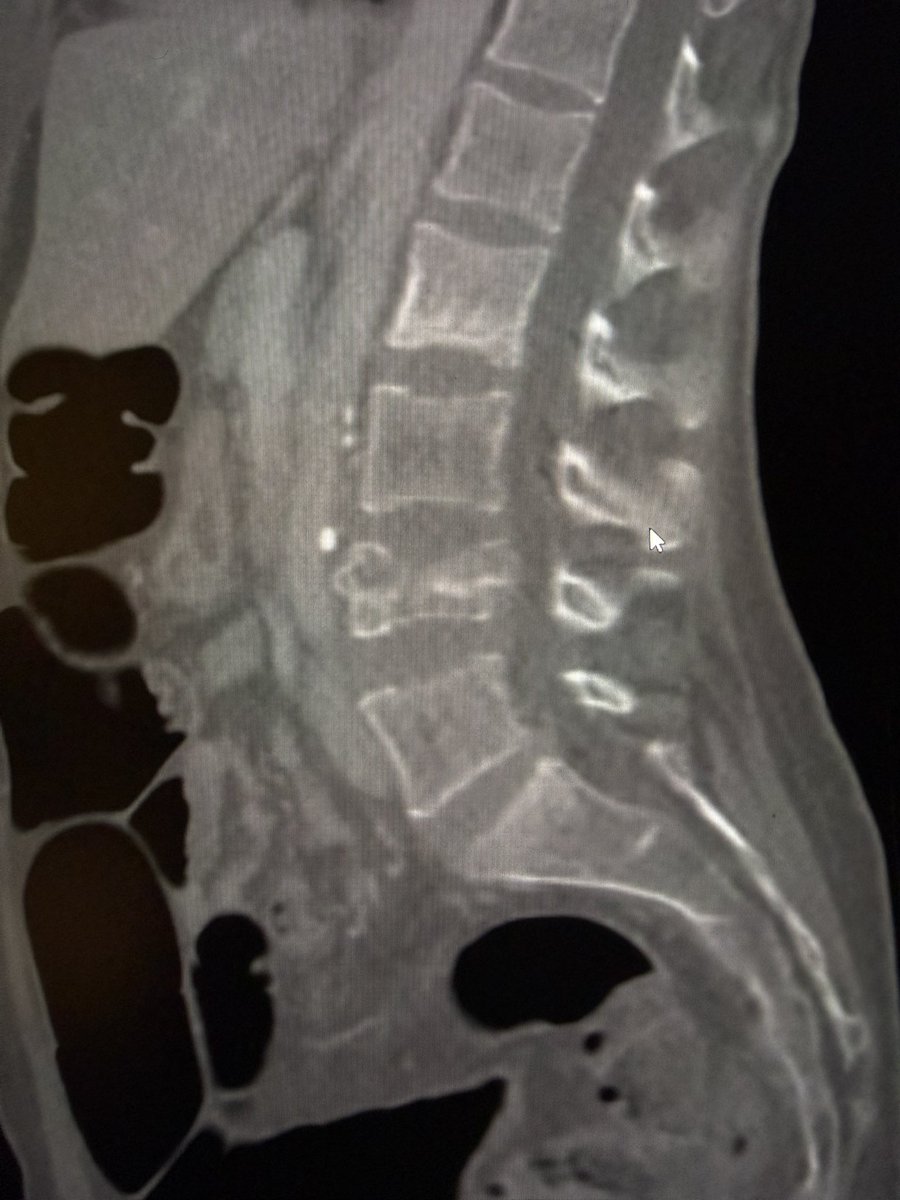

Satisfying height restoration with lumbar spinejack - bone lifted along the horizontal fracture plane and cement filled void nicely. #kyphoplasty #VCF #Trauma @AlanAlperMD